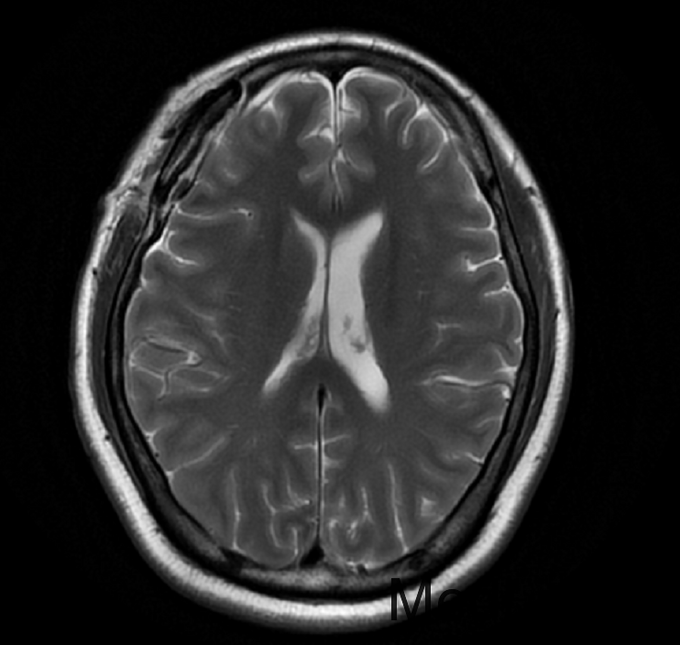

查体:双侧瞳孔等大等圆,直径约3mm,左侧对光反射灵敏,右侧对光反射迟钝,动眼自主,额纹对称,嘴角伸舌无歪斜。 2015-08-22当地医院查头颅MRI示:“右蝶骨嵴脑膜瘤”。

初步诊断:右]蝶骨嵴脑膜瘤。入院完善相关检查及术前准备,(2015-09-227日行磁共振(头部)检查提示:右侧蝶骨脊区占位,建议MRI增强。2015-09-29DSA示:右侧颈内动脉交通段、眼段狭窄,右侧前交通胚胎型,左侧椎动脉优势供血。垂体磁共振造影示:右侧蝶骨脊区占位,考虑脑膜瘤。排除手术禁忌症后于2015-09-29日行:开颅肿瘤切除术。